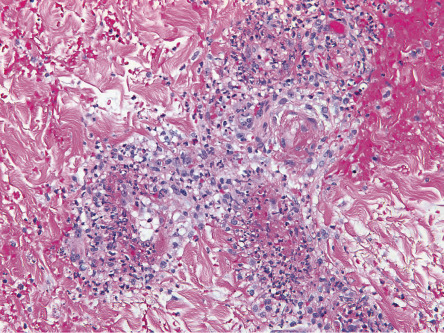

In cutaneous vasculitis, the histologic findings vary depending upon the type and age of the sampled lesion in addition to the size of the affected vessel. The classic histopathologic features of CSVV are referred to as LCV and consist of transmural infiltration of the walls of small vessels (primarily postcapillary venules) by neutrophils undergoing karyorrhexis of their nuclei, as well as fibrinoid necrosis of the damaged vessel walls ( Fig. 24.4 ). Other findings include leukocytoclasia (degranulation and fragmentation of neutrophils, leading to the production of nuclear dust), extravasated erythrocytes, and signs of endothelial cell damage. However, lesions present for greater than 48 to 72 hours may have a predominantly mononuclear rather than neutrophilic infiltrate. Palpable purpura, the most common clinical lesion of CSVV, can be explained by the infiltrate of leukocytes (palpability) and the resulting extravasation of RBCs from the damaged blood vessel (purpura).

Additional histological findings may provide clues to the underlying etiology, e.g. eosinophils in drug-induced CSVV (up to 100% of cases) , thrombi plus CSVV in patients exposed to levamisole-tainted cocaine, and thrombi plus dense dermal inflammation in septic vasculitis. Involvement of deeper dermal vessels alerts the clinician to look for an underlying etiology rather than presuming the CSVV is idiopathic .

Vasculitis of medium-sized blood vessels is characterized by similar changes involving the vessels (e.g. small arteries) of the deep reticular dermis and subcutaneous fat. Neovascularization of the adventitia, in the form of small capillaries, is commonly seen in older lesions of medium-sized vessel vasculitis.